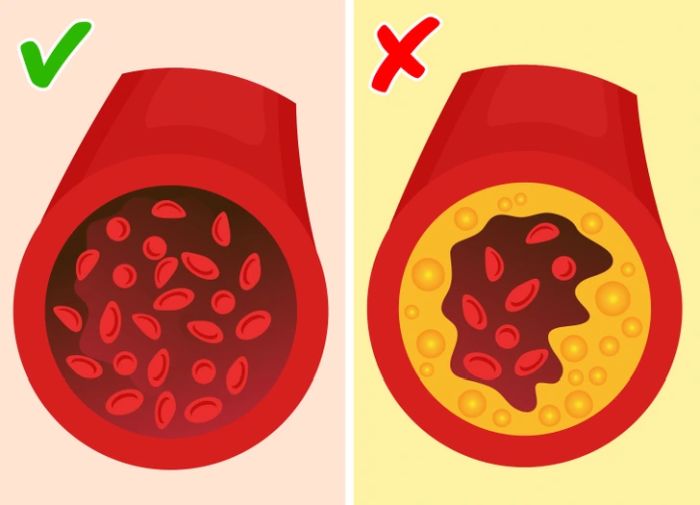

Sok várandós nő fogyaszt koffeinmentes kávét az alacsonyabb koffeinbevitel érdekében. De csak mert a koffeinmentes kávéban kevesebb a koffein, még nem jelenti, hogy biztonságos belőle sokat inni. Az orvosok szerint napi egy bögre kávé a terhes nőknek teljesen biztonságos, de koffeinmentesből sem szabad túlzásba esni.

Könnyű megfeledkezni róla, hogy a koffeinmentes kávéban is van bizonyos mennyiségű koffein, amit a máj ugyan képes lebontani, ám a baba teste nem tudja ugyanezt megtenni. Bár alacsonyabb a koffeintartalma, mint a hagyományos kávénak, az orvosok mégis azt javasolják a várandósoknak, hogy napi egy csészénél többet ne fogyasszanak belőle.